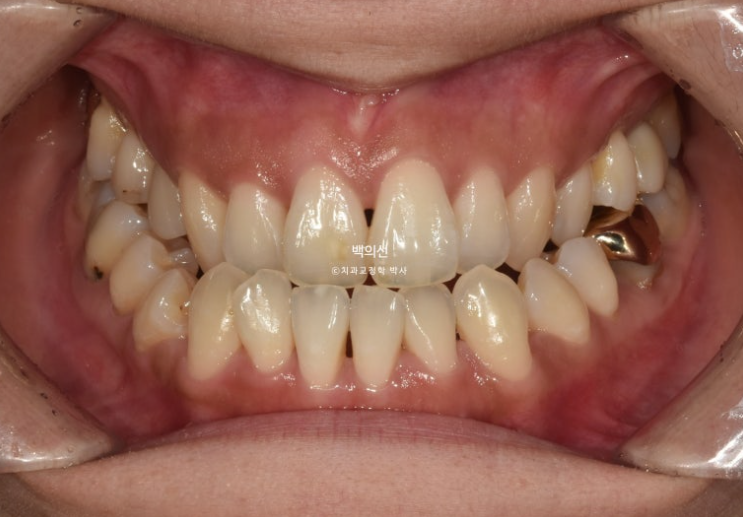

1년반전, 교정치료를 위해 오신 30대 환자분입니다.

오래 전 교정상담을 받은 적이 있고 양악수술을 권유받아 교정도 단념하고 살던 차에, 가족 교정상담차 오셨다가 함께 상담을 받게 되었습니다.

앞니뿐만 아니라 큰어금니까지 반대교합입니다.

앞니 중심선은 약 2mm 어긋나 있습니다.

어금니 역시 심한 3급 교합관계를 보입니다. 앞니는 반대교합으로 거꾸로 물립니다.

왼쪽 위 큰어금니 1개가 임플란트이며 앞니가 삐뚤삐뚤합니다.

주걱턱 부정교합은 아래 앞니를 지지하고 있는 치조골이 얇은 경우가 많습니다.

그만큼 블랙트라이앵글의 발생 위험도 높죠. 이부분을 개선하기 위한 치간삭제가 들어가겠지만 그래도 어느정도 블랙트라이앵글은 감안해야 하는 부분입니다.